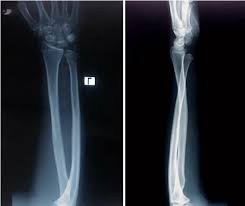

X-ray Left Forearm AP & LATERAL

An X-ray Left Forearm AP & LAT captures both front-to-back (AP) and side (LAT) views of the left forearm, including the radius and ulna bones. This x-ray helps diagnose fractures, dislocations, infections, and joint conditions like arthritis. Doctors often recommend it for individuals experiencing pain, swelling, or restricted movement due to an accident or repetitive strain.

An X-ray Left Forearm AP & Lateral is a medical imaging test that takes two views—front (AP) and side (lateral)—of the left forearm bones.

It helps doctors examine the radius and ulna for fractures, dislocations, infections, or other abnormalities..Why is it Done?